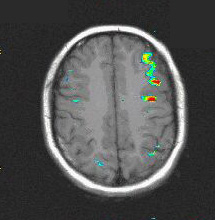

Caso 2

Paciente Paciente de sexo masculino de 13 años de edad.  Mapeo prequirúrgico de áreas elocuentes.

Paradigma Fluidez fonética

ACTIVADO: Generación en silencio de palabras que comienzan con una letra dada

DESACTIVADO: No pensar en nada

Resultados Fuerte activación en las circunvoluciones frontales inferiores y medias izquierdas, y el surco postcentral izquierdo.   No se observó ninguna activación significativa en el  hemisferio derecho.